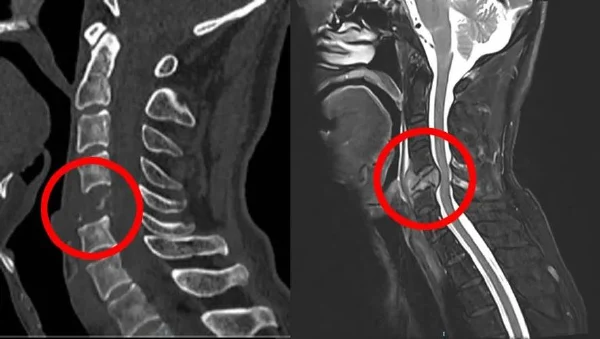

根据患者的病历记录,该患者因右上肢疼痛麻木而前来就诊,病程已持续两个月。在进行增强MRI检查后,发现其颈椎第六节椎管内有占位性病变,也就是颈椎肿瘤。患者的体格检查显示一般情况良好,无明显外观异常。各项生命体征包括血压、心率、呼吸频率和体温均在正常范围内。

颈椎肿瘤的出现会压迫周围组织,特别是神经根和脊髓,这会导致一系列症状,如疼痛、麻木、肌肉无力等。严重时,肿瘤可能会引起脊髓压迫症,导致瘫痪等严重后果。